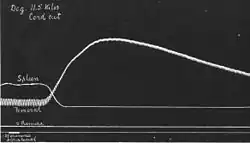

A new chapter was opened when Max Lewandowsky in 1899 in Berlin observed that adrenal extracts acted on the smooth muscle of the eye and orbit of cats—such as the iris dilator muscle and nictitating membrane—in the same way as sympathetic nerve stimulation.[27] The correspondence was extended by John Newport Langley and, under his supervision, Thomas Renton Elliott in Cambridge. In four papers in volume 31, 1904, of the Journal of Physiology Elliott described the similarities organ by organ. His hypothesis stands in the abstract of a presentation to the Physiological Society of May 21, 1904, a little over ten years after Oliver and Schafer's presentation:[28] "Adrenalin does not excite sympathetic ganglia when applied to them directly, as does nicotine. Its effective action is localized at the periphery. I find that even after complete denervation, whether of three days' or ten months' duration, the plain muscle of the dilatator pupillae will respond to adrenalin, and that with greater rapidity and longer persistence than does the iris whose nervous relations are uninjured. Therefore, it cannot be than adrenalin excites any structure derived from, and dependent for its persistence on, the peripheral neurone. ... The point at which the stimulus of the chemical excitant is received, and transformed into what may cause the change of tension of the muscle fiber, is perhaps a mechanism developed out of the muscle cell in response to its union with the synapsing sympathetic fiber, the function of which is to receive and transform the nervous impulse. "Adrenalin" might then be the chemical stimulant liberated on each occasion when the impulse arrives at the periphery." The abstract is the "birth certificate" of chemical neurotransmission.[29] Elliott was never so explicit again. It seems he was discouraged by the lack of a favorable response from his seniors, Langley in particular, and a few years later he left physiological research.

- The 'birth certificate' of chemical neurotransmission

-

-